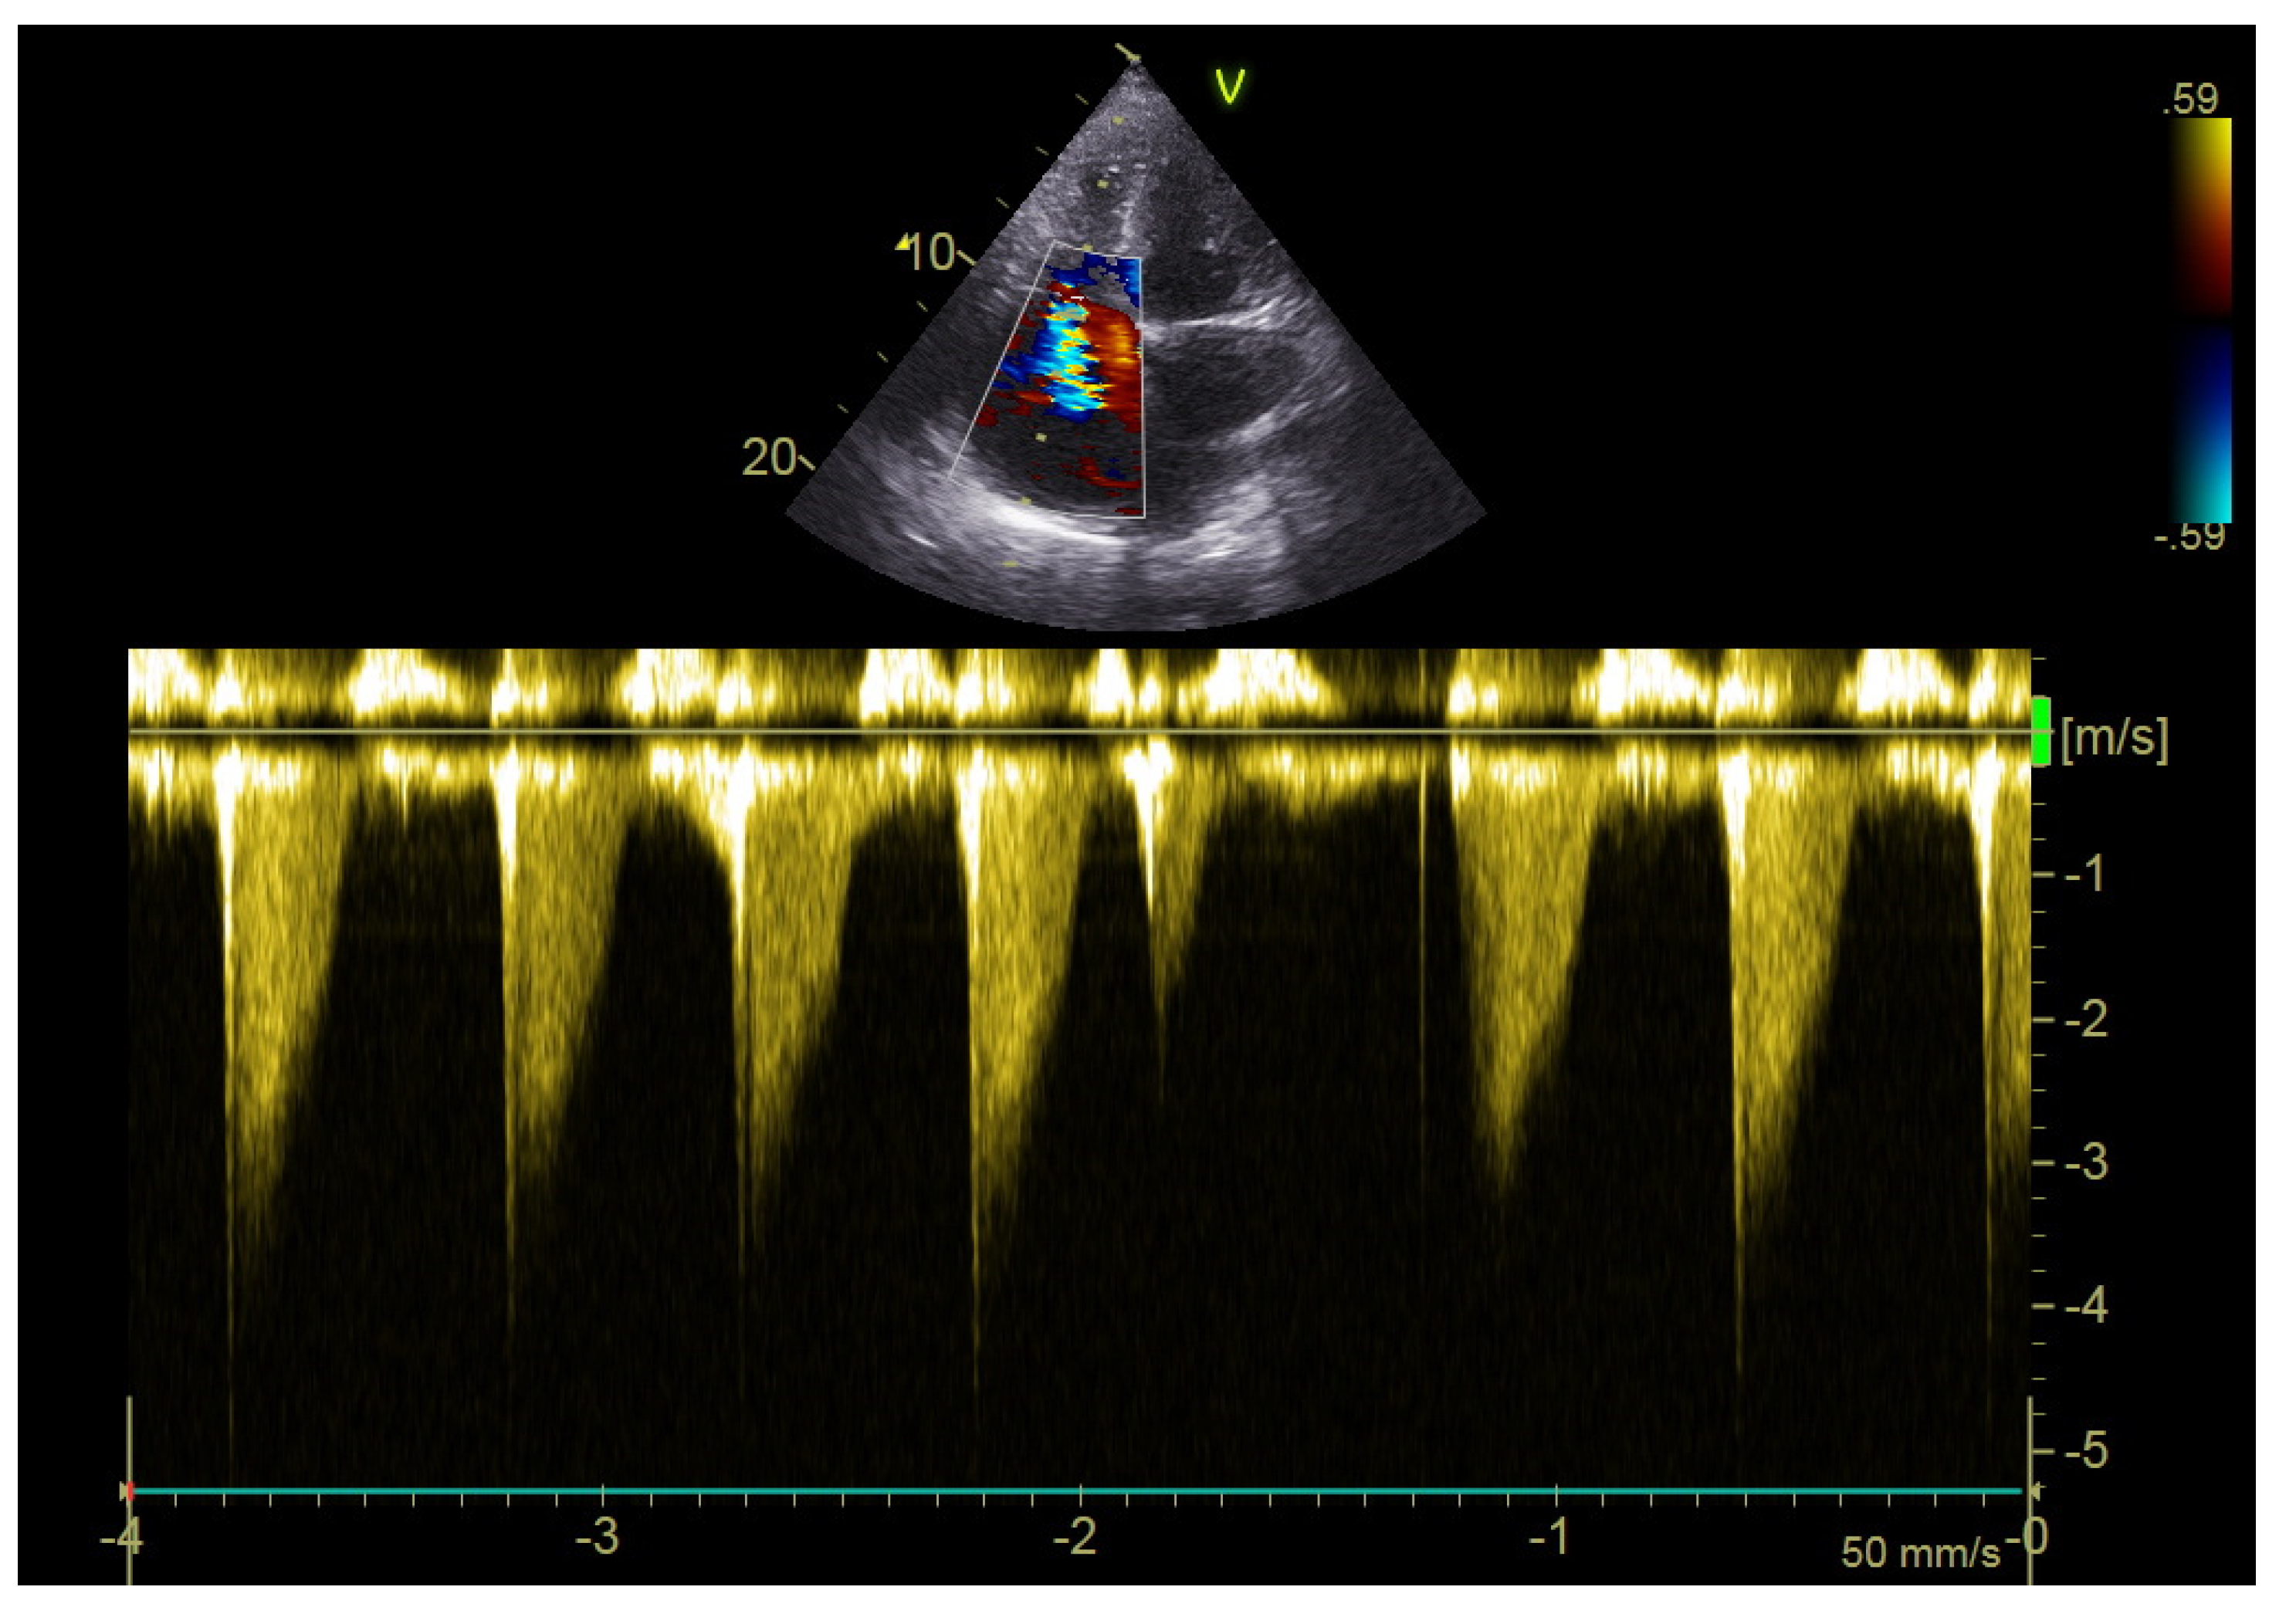

2.4. Echocardiography

| LV ejection fraction (%), mean ± sd | 57 ± 10 |

| Right ventricular diameter (mm), mean ± sd | 29 ± 6 |

| Right/left ventricular diameter ratio, mean ± sd | 0.64 ± 0.11 |

| Right atrial area (cm2), mean ± sd | 17.3 ± 5.3 |

| TAPSE (mm), mean ± sd | 23 ± 4 |

| S’RV (cm/s), mean ± sd | 16 ± 3 |

| PVAT (msec), mean ± sd | 120 ± 25 |

| RV ESP (mmHg), mean ± sd | 36 ± 11 |

| VCI (mm), mean ± sd | 15 ± 2 |

| Signs of deep vein thrombosis on color Doppler, yes, n (%) | 9 (28.1) |